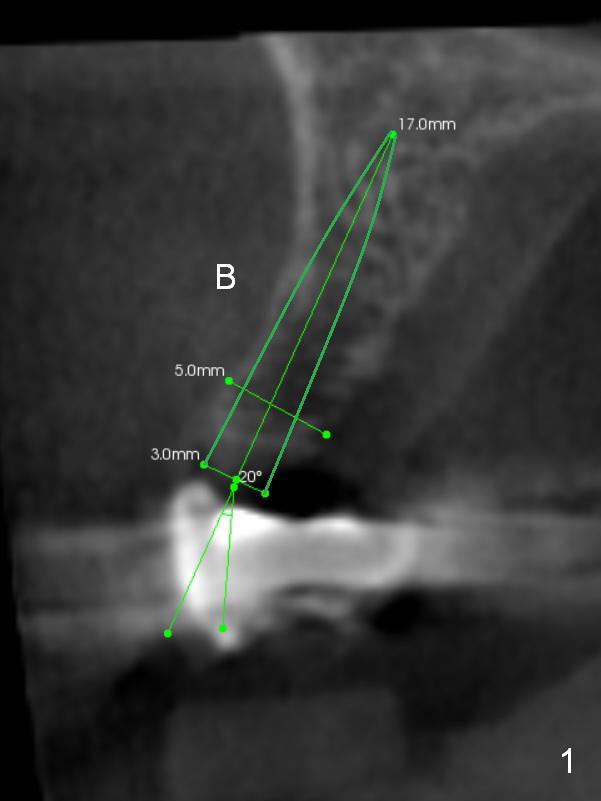

A 59-year-old lady had a brain stem tumor removed ~ 20 years ago. The surgery left her tongue paralyzed (cranial nerve #12). She mainly chews on the right side. Porcelain has been chipped from #2 crown and #3 retainer. Treatment plan includes removal of #4 pontic (Fig.2 CT coronal section (B: buccal)), implant placement (Fig.1), and crown placement at #2-4 once the implant osteointegrates. Since the ridge at #4 is narrow buccopalatally, a 3 mm 1-piece angled (15°) implant is to be placed. Use the corresponding 3 mm tissue punch for access after palpation of the ridge. Bone density in the area is low (-300 to 300 Hounsfield units). Underprep is a must.